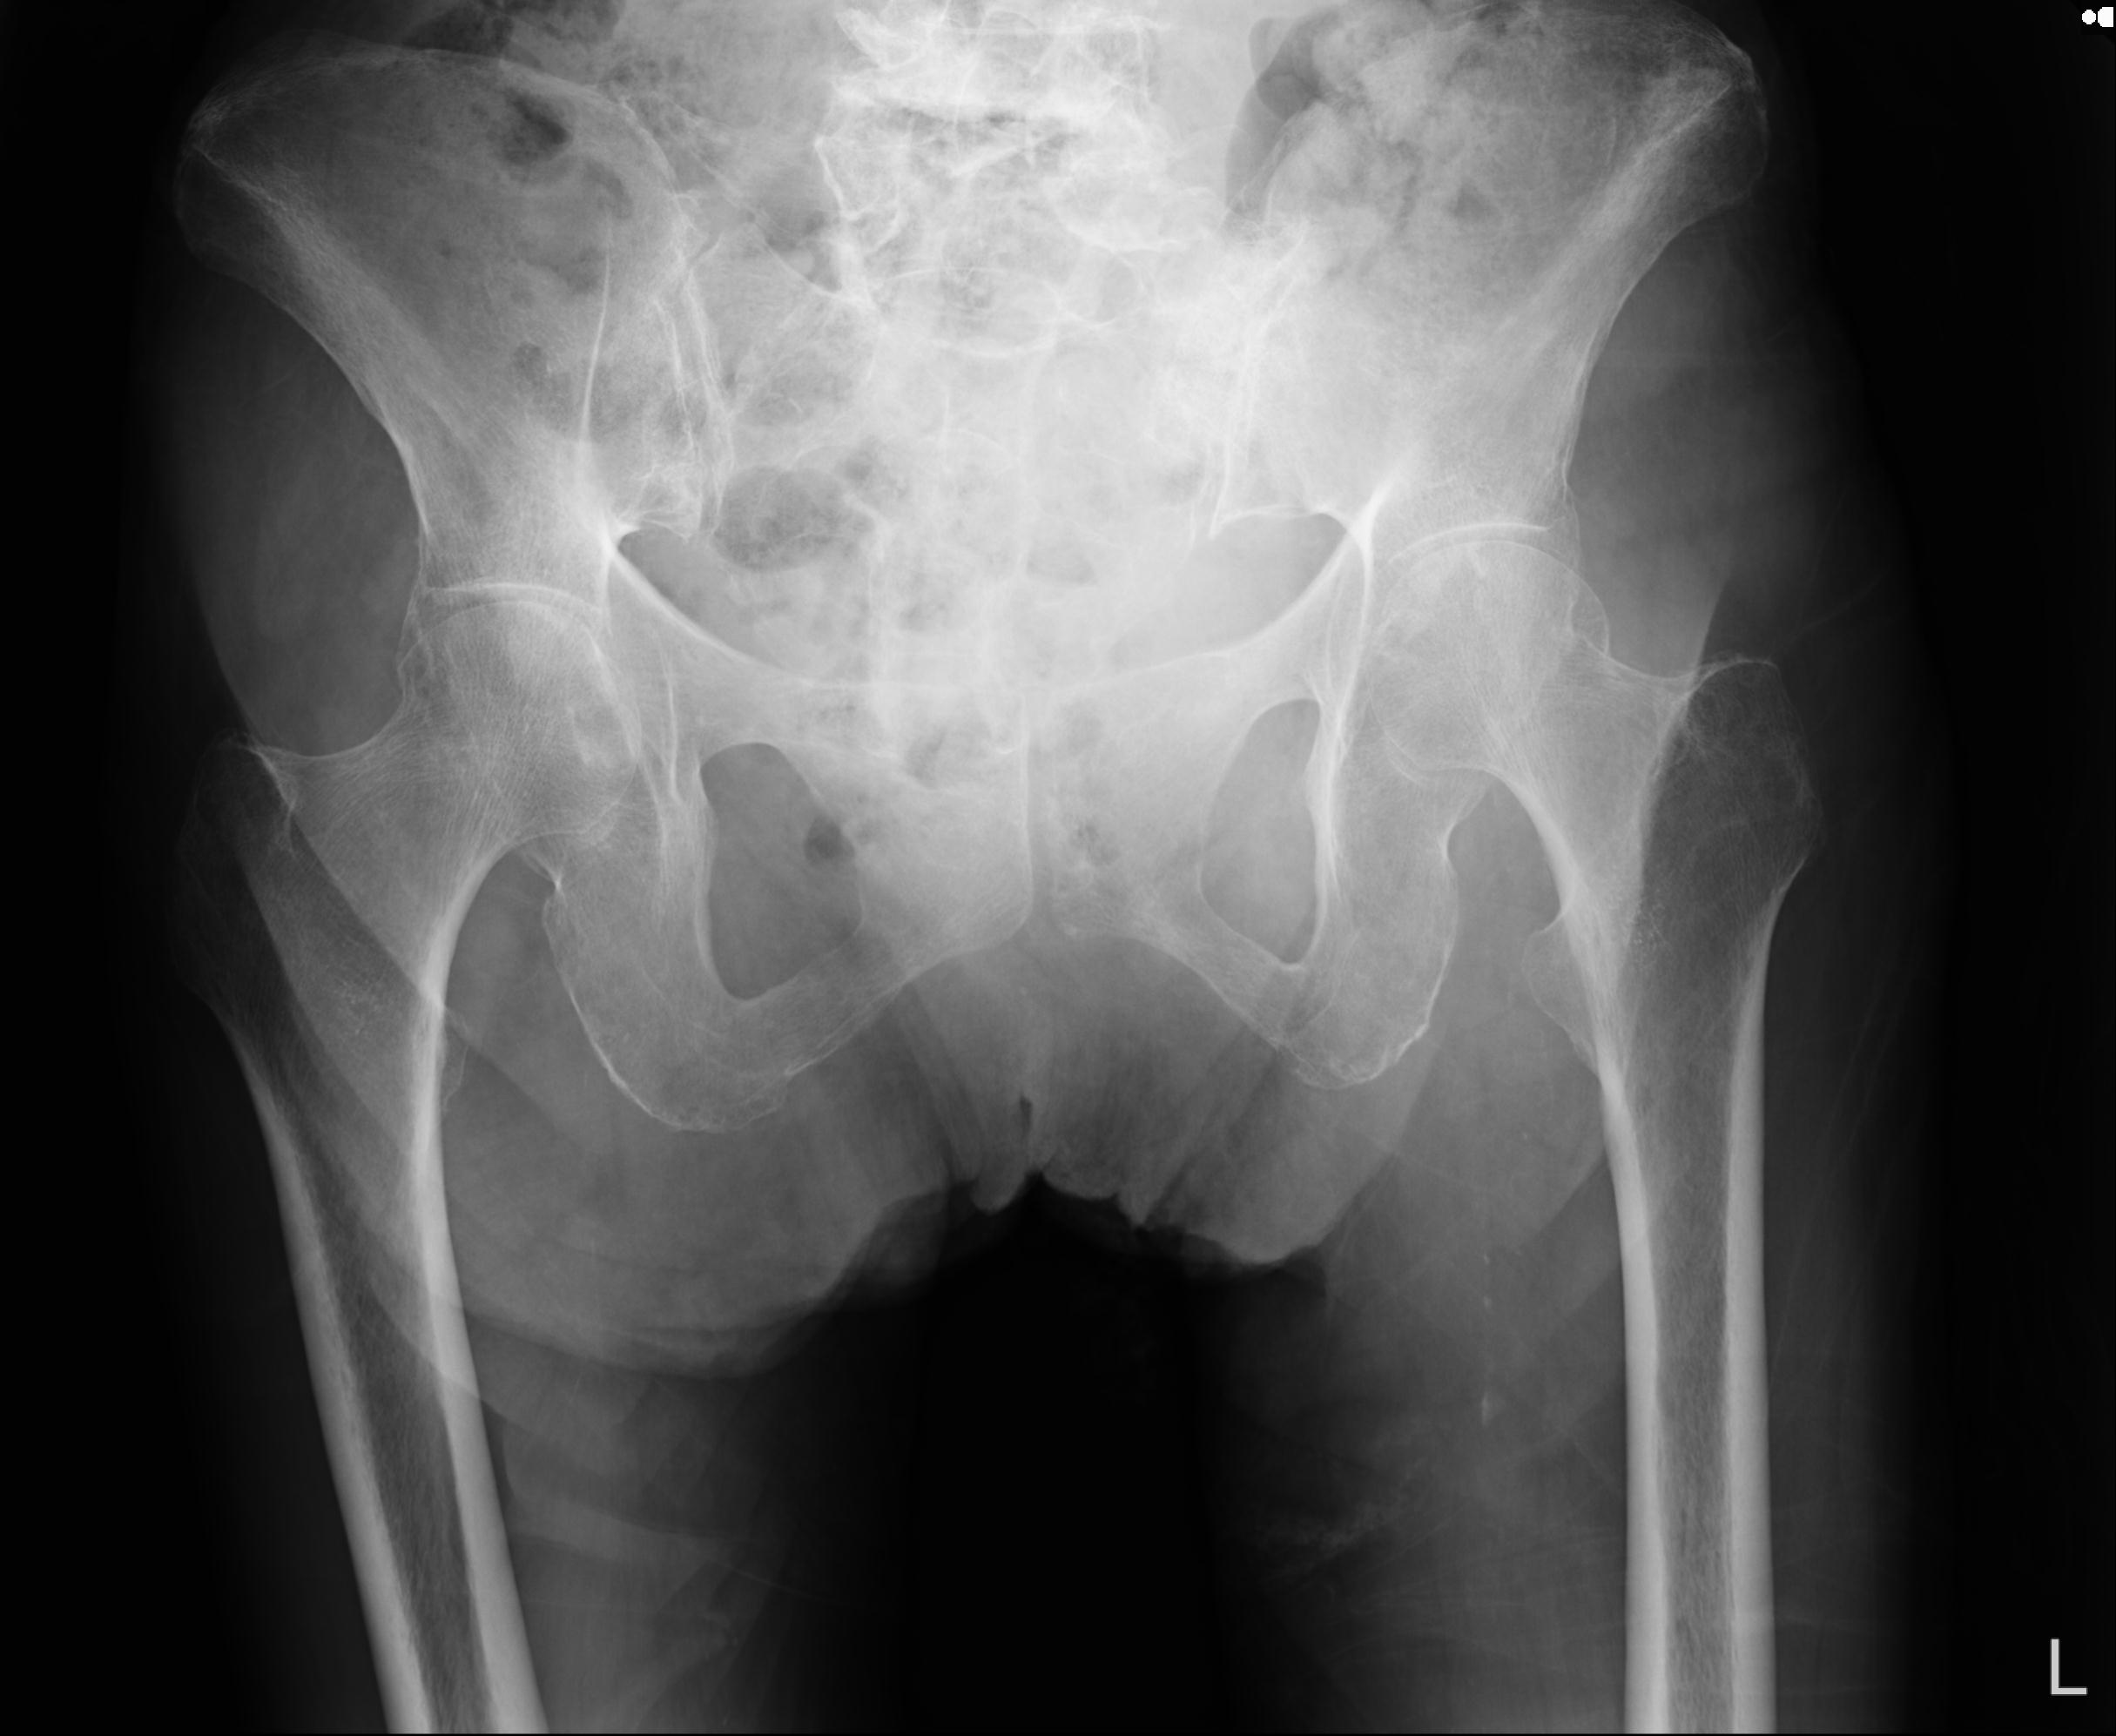

100703 1/27 両股正面+軸 1/29 両股正面+軸 94歳女性 パンソンロン